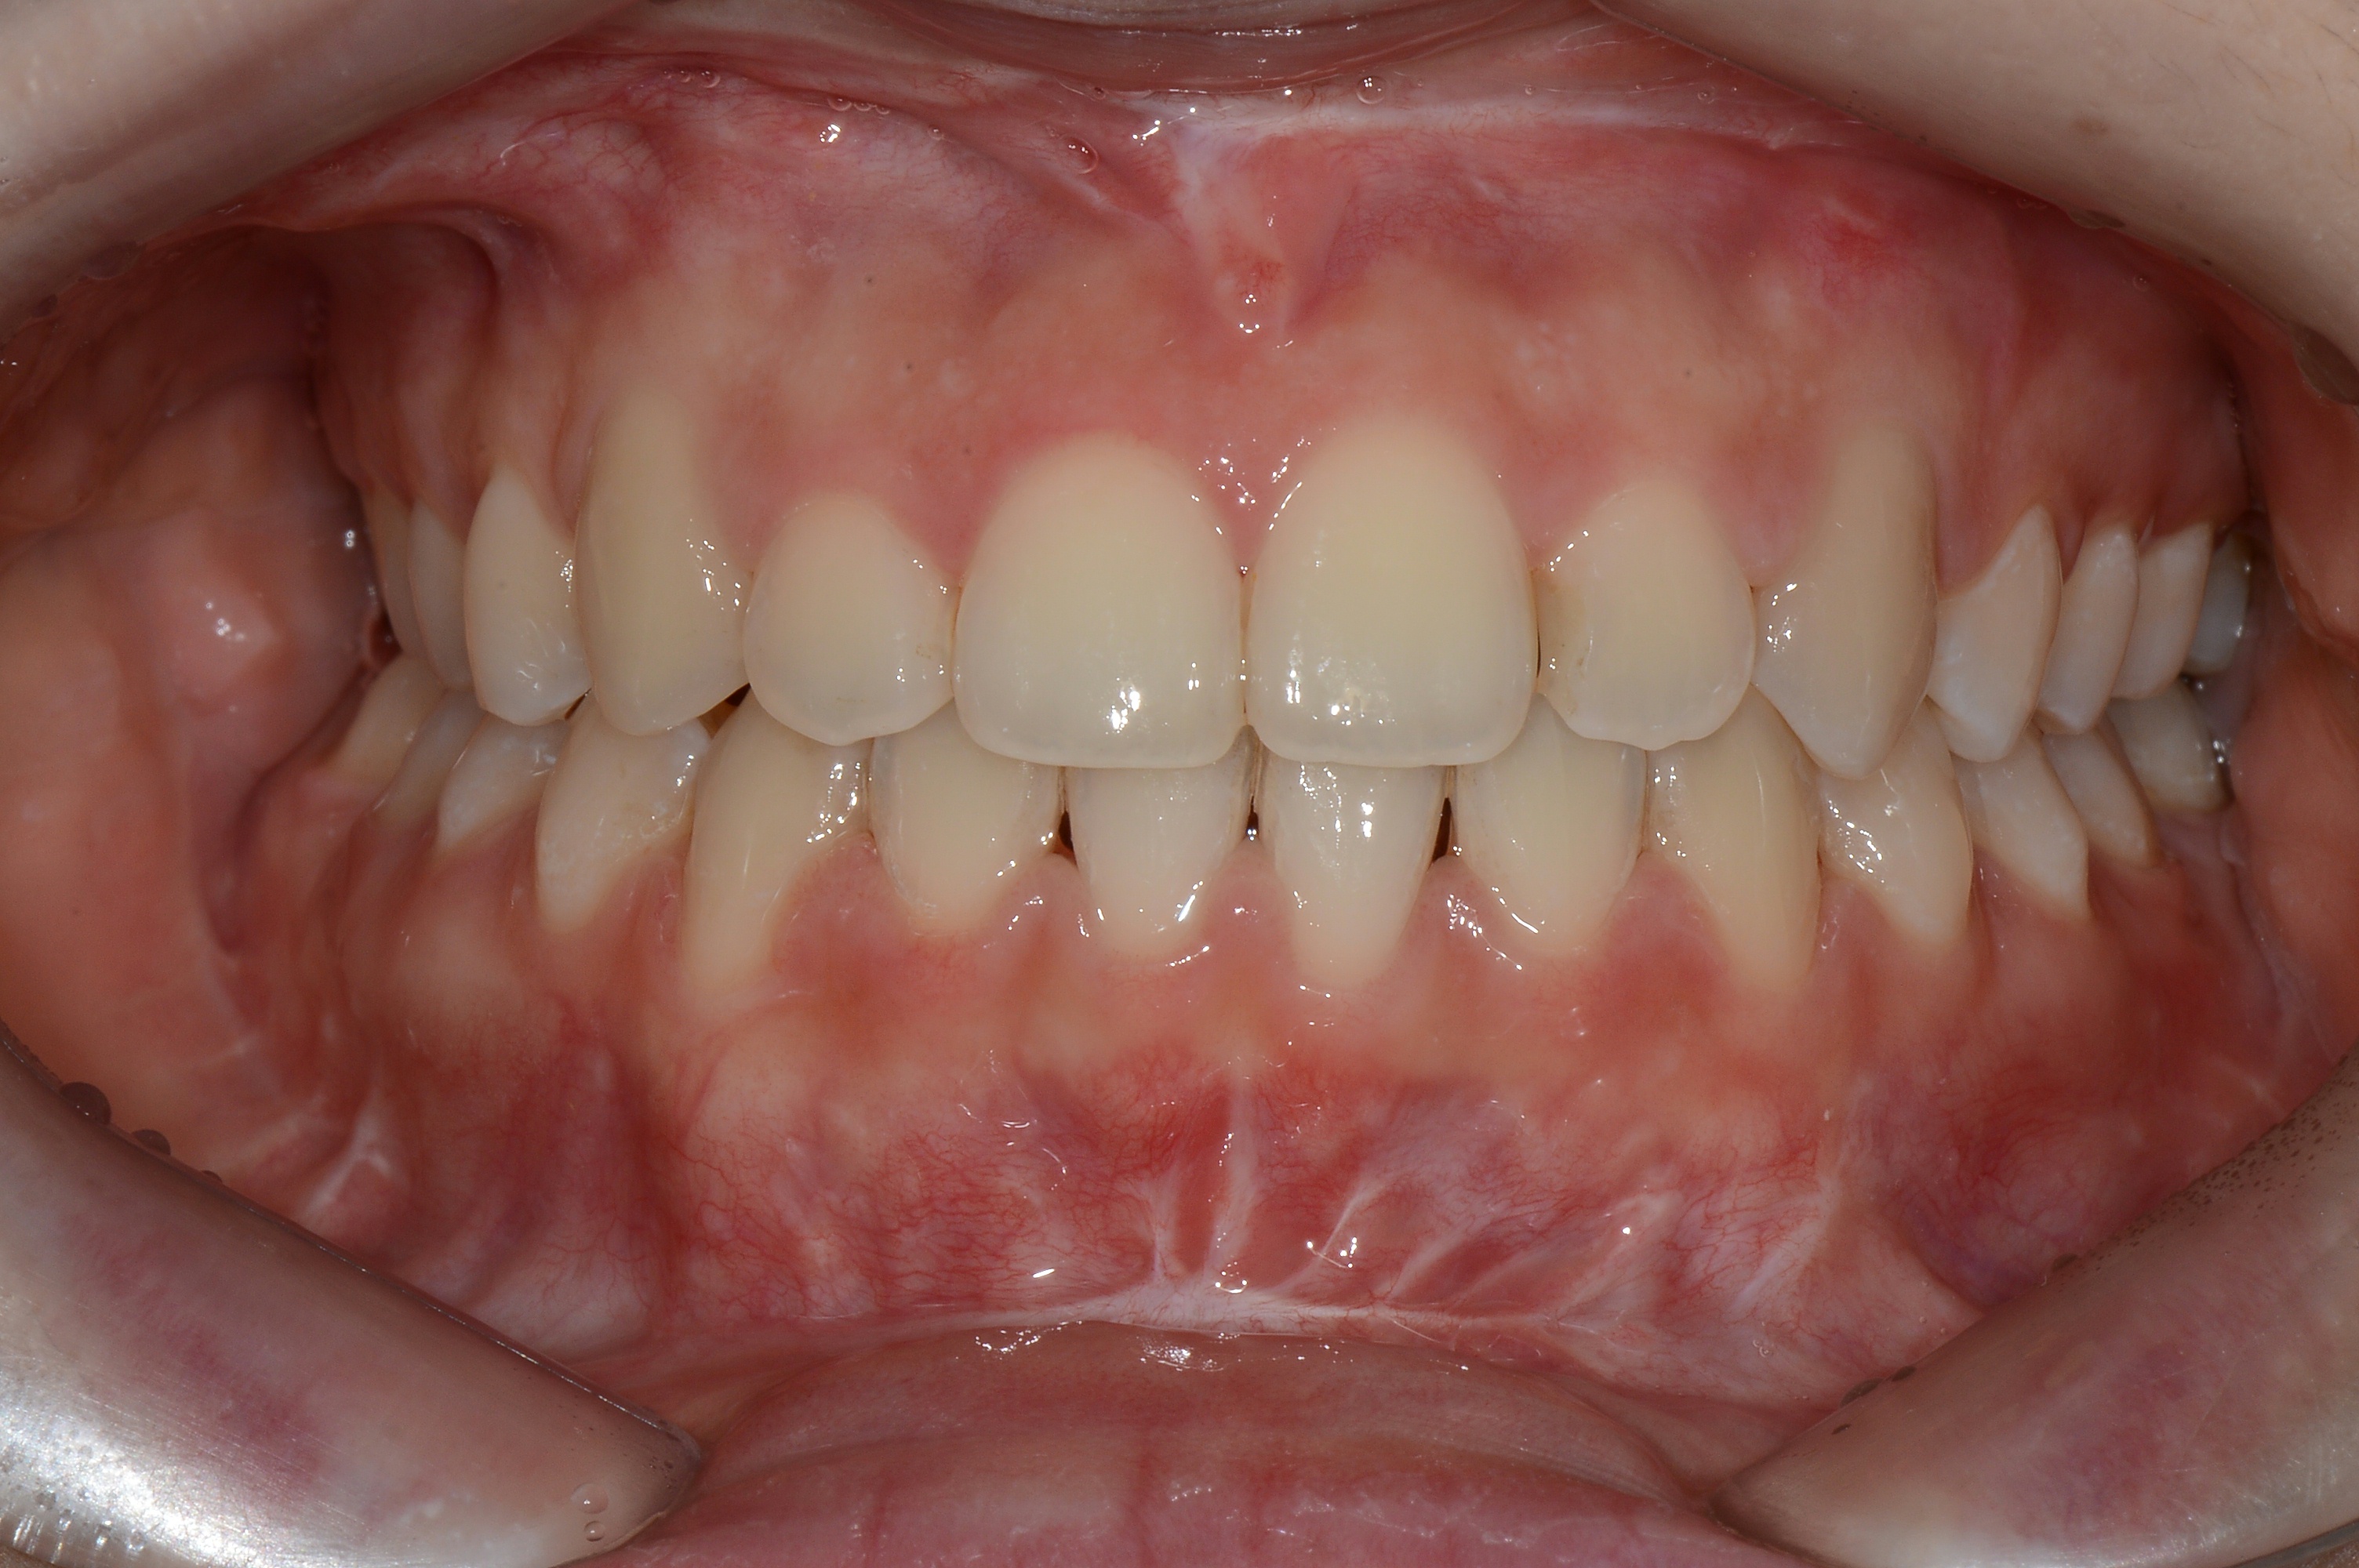

치료 전 사진입니다.